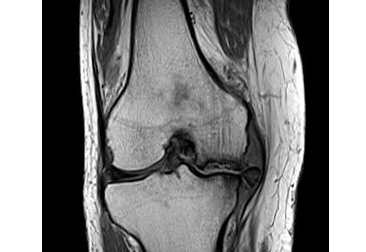

根据MRI影像,诊断为变形性膝关节病 等级4(末期)。

股骨内侧突发性骨坏死,半月板外周滑脱

白色部分膝盖股关节积液